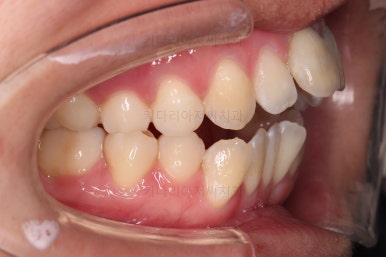

1. 초진

부산개방교합 키다리아저씨치과에 처음 내원 시 입안의 모습입니다.

전반적으로 치열이 삐뚤고요.

앞니쪽이 다물어지지 않는 개방교합(오픈바이트, open bite) 을 보였습니다.

어금니 맞물림을 보면 앵글씨 2급 부정교합 양상이어서 위아랫니가 모두 1대1로 부딪히고 있는 상태였습니다.